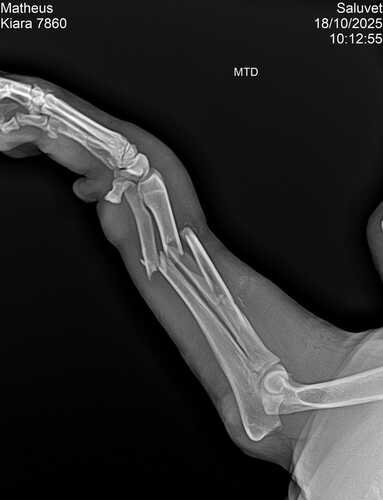

Olá boa noite me chamo Matheus tenho um casal de pet da raça pitbull e infelizmente recente na sexta feira ele tiveram uma briga feia na qual meu cachorro macho Zeus quebrou a pata da kiara e desde então estou atrás de ajuda ONGs ou até mesmo clínica mais em conta só que até agora os valores saíram completamente do meu orçamento amo meus cães e não desejo isso a ninguém ver a situação e infelizmente não poder solucionar o problema mas estou vindo através das redes sociais pedir a ajuda que vcs com qualquer quantia que tocar no coração de cada um a cirurgia dela tem que ser feita por um médico ortopedista e os valores não são baratos mas com a ajuda e colaboração de todos creio que dará certo no momento estou tratando dela apenas com antibióticos

Quem sentir no coração e quiser conhecer o caso mais a fundo tenho o raio X e mando fotos ou vídeos de como ela se encontra no momento obrigado